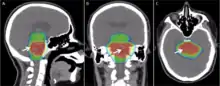

Modern radiation therapy relies on a CT scan to identify the tumor and surrounding normal structures and to perform dose calculations for the creation of a complex radiation treatment plan. The patient receives small skin marks to guide the placement of treatment fields.[10] Patient positioning is crucial at this stage as the patient will have to be placed in an identical position during each treatment. Many patient positioning devices have been developed for this purpose, including masks and cushions which can be molded to the patient. Image-guided radiation therapy is a method that uses imaging to correct for positional errors of each treatment session.

Delivery parameters of a prescribed dose are determined during treatment planning (part of dosimetry). Treatment planning is generally performed on dedicated computers using specialized treatment planning software. Depending on the radiation delivery method, several angles or sources may be used to sum to the total necessary dose. The planner will try to design a plan that delivers a uniform prescription dose to the tumor and minimizes dose to surrounding healthy tissues.

The planning of radiation therapy treatment has been revolutionized by the ability to delineate tumors and adjacent normal structures in three dimensions using specialized CT and/or MRI scanners and planning software.[72]

Virtual simulation, the most basic form of planning, allows more accurate placement of radiation beams than is possible using conventional X-rays, where soft-tissue structures are often difficult to assess and normal tissues difficult to protect.

An enhancement of virtual simulation is 3-dimensional conformal radiation therapy (3DCRT), in which the profile of each radiation beam is shaped to fit the profile of the target from a beam's eye view (BEV) using a multileaf collimator (MLC) and a variable number of beams. When the treatment volume conforms to the shape of the tumor, the relative toxicity of radiation to the surrounding normal tissues is reduced, allowing a higher dose of radiation to be delivered to the tumor than conventional techniques would allow.[10]